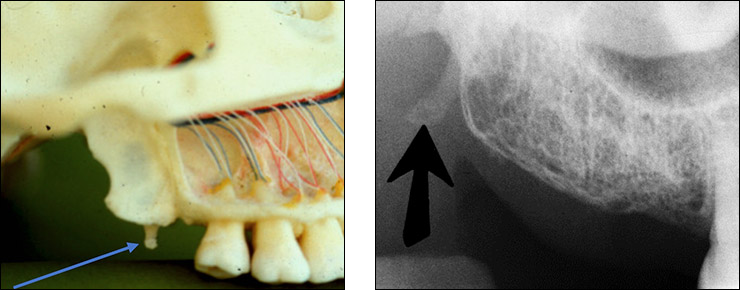

lingual foramen

tiny hole in internal surface of mandible near midline

small radiolucent dot located inferior to the apices of mandibular incisors, may be seen

genial tubercles

tiny bumps of bone located on lingual aspect of mandible

ringshaped radiopacity surrounding lingual foramen, may be viewed